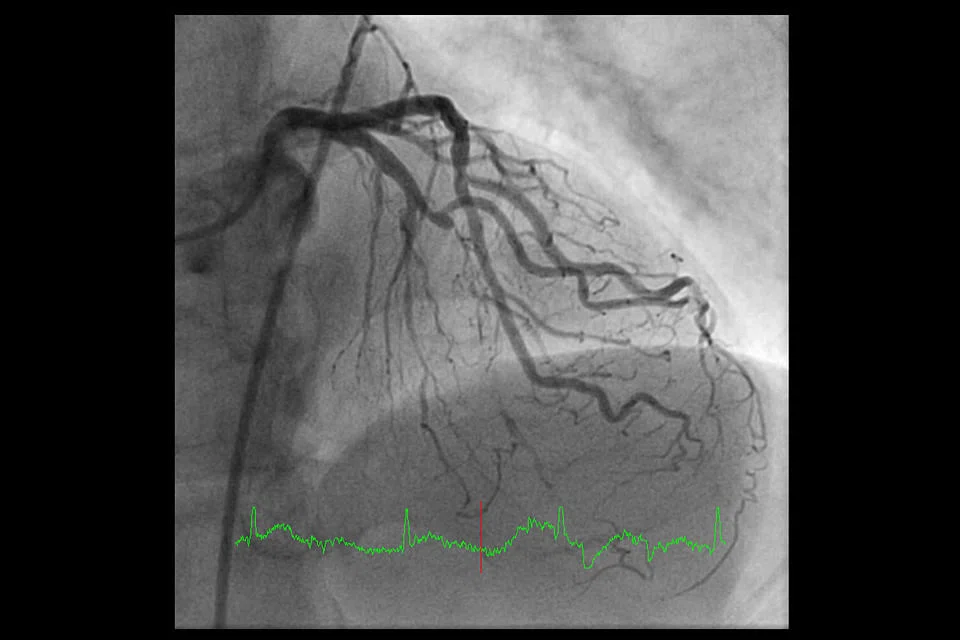

MR A was found to have severe blockage of all the three major heart arteries resulting in compromised blood flow to the heart. This caused his heart to be significantly swollen and his pumping action of his left heart chamber (left ventricle or LV) was significantly impaired.